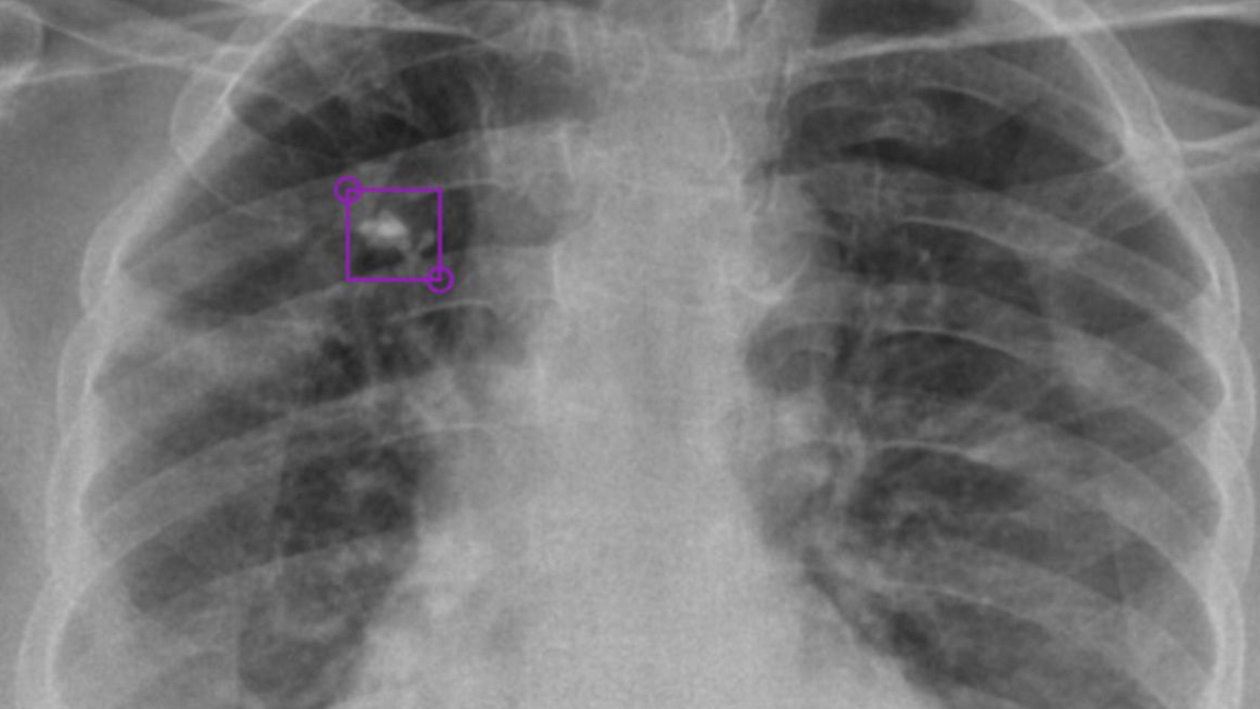

Diagnosis kanker paru reality Senin 21 Maret 2011 Diagnosis kanker paru Kanker paru-paru biasanya dicurigai pada individu-individu yang memiliki temuan radiografi dada tidak normal atau memiliki gejala yang disebabkan oleh efek baik lokal maupun sistemik tumor. In reality as I work for a weekly magazine I constantly receive positive or negative comments on my work. About Press Copyright Contact us Creators Advertise Developers Terms Privacy Policy Safety How YouTube works Test new features Press Copyright Contact us Creators.

Gejala klinis kanker paru Pada dasarnya perjalanan kanker paru melalui tiga stadium periode dimana kurang lebih dalam setahun terjadi peningkatan jumlah sel yang atipik yang bisa diketahui dalam pemeriksaan sitologi sputum kemudian periode dimana terjadi progresivitas sel atipi pada karsinoma in situ.

Lebih lanjut seorang ilmuwan dan Chief of Thoracic Surgery di George Washington University Hospital Keith Mortman berhasil melakukan pemindaian dan menggambarkan kondisi kesehatan paru-paru pasien COVID-19 dengan menggunakan teknologi Virtual Reality VR. Už je niekoľko dní jasné že o rozprávkovú výhru 100 000 eur zabojuje víťazka šou Farma 12 Xénia Gregušová. Volume Residu VR Volume residu yaitu volume udara yang masih tetap berada dalam paru-paru setelah ekspirasi kuat kira-kira sebanyak 1000 mililiter.

Priyanka Chopra i Nick Jonas. JAKARTA- Ilmuwan dan Kepala Bedah Thoracic di Rumah Sakit Universitas George Washington Keith Mortman berhasil memindai gambar paru-paru PASIEN COVID-19 dengan teknologi Virtual Reality VR. Dalam menguraikan proses respirasi terkadang diperlukan penyatuan dua atau lebih jenis-jenis volume di atas.

Pemindaian tersebut ditampilkan memanfaatkan teknologi virtual reality atau VR. AUGMENTED REALITY IMPLEMENTATIONS OF 3D MODELING ASTHMA ATTACKS ON THE LUNGS ABSTRACT Asthma is an inflammatory disease of the airways that causes narrowing of the airways which causes shortness of breath or. BRATISLAVA - Od vraždy Jána Kuciaka a jeho snúbenice Martiny Kušnírovej v dome vo Veľkej Mači už čoskoro uplynú štyri roky a pre rodičov aj blízkych je stále bolestné sa k nedávnej tragédii vracať.

Kondisi Paru-paru Pasien Corona dari Virtual Reality. Kondisi ini membuat Pak Ogah harus dilarikan ke rumah sakit Kartika Husada Jati Asih Bekasi.